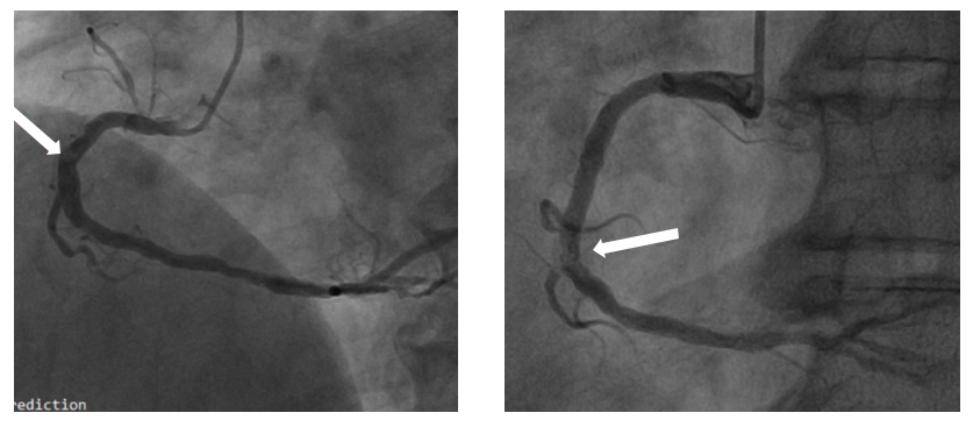

图5.冠状动脉造影的钙化识别和特征。注:白色箭头指示充盈缺损,后腔内影像学证实为钙化结节。

图6.钙化结节的冠状动脉造影特征。冠状动脉造影特征,CNs呈透亮区(白色箭头)。IVUS (A1)和OCT (B1,C1)证实钙化结节。CN:钙化结节(calcified nodule)。